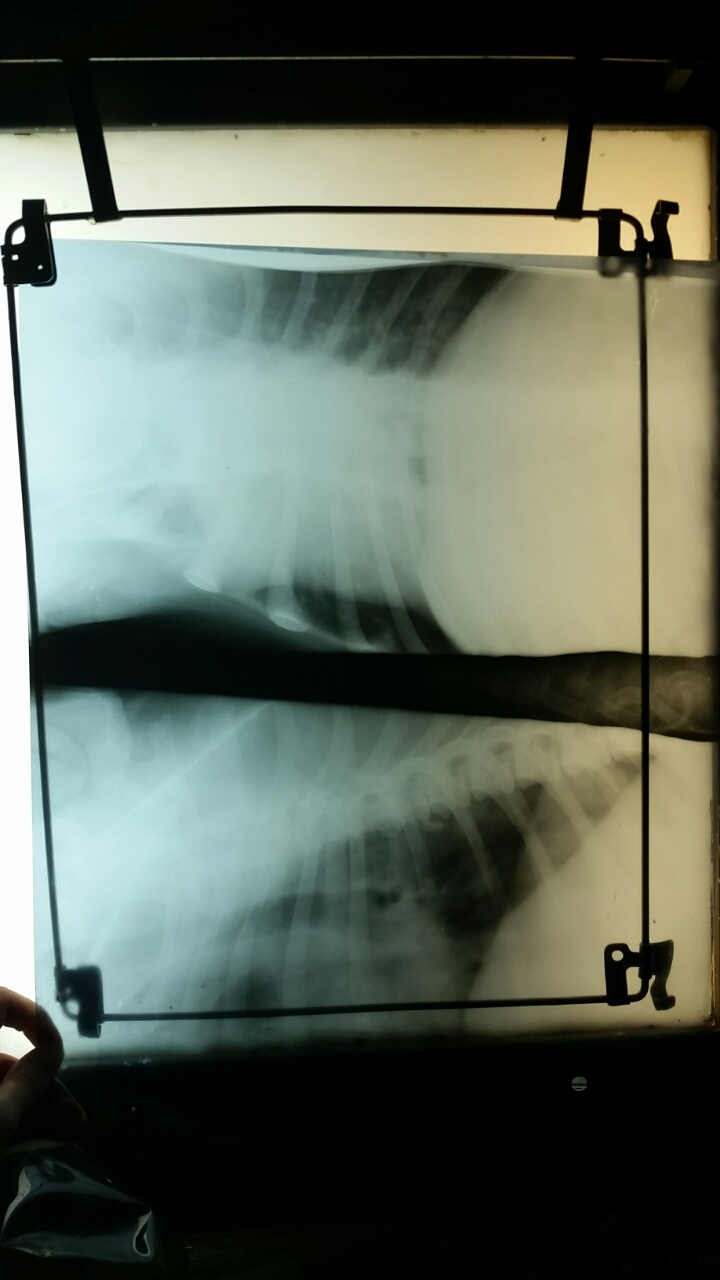

Рентген.

Вложения

image-3dfda32f78ab1fdd032b17d680d7d3ec74251f91873abff76728344aa4334e5b-V.jpg